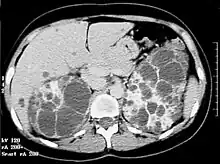

Le scanner n'est pas nécessaire en première intention, même s'il visualise parfaitement les kystes, qu'ils soient rénaux ou hépatiques. l'IRM permet de quantifier le volume rénal, ce dernier étant corrélé avec le risque évolutif[16].

L'augmentation de la taille des deux reins est, en règle générale, symétrique[17].